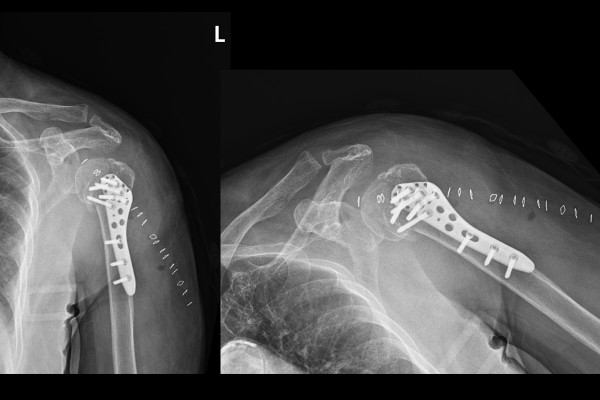

정확한 상태를 파악하기 위해 촬영한 X-RAY에서 어깨 상완골 3분위 골절이 확인 되었고,

수술 후 X-RAY를 보면 어긋난 골절선 없이 강하게 금속판 고정이 잘 된 것이 확인됩니다.